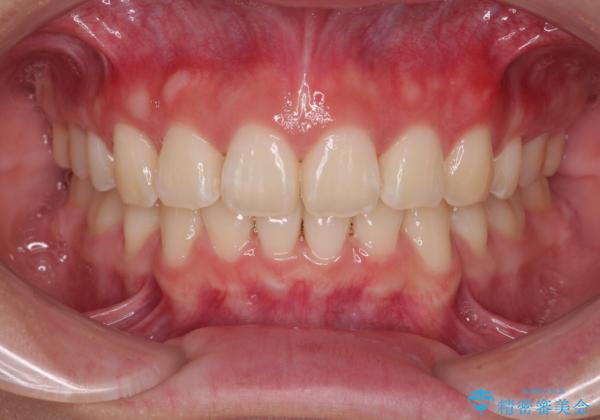

口元が出ているのを改善したい。 クリアブラケットによる抜歯矯正

- 前歯部のデコボコと口元が出ているのが気になるとのことで来院された患者様です。

口元の突出感の解消と、このままデコボコを解消するとさらに出っ歯傾向になってしまうことを考慮し、上下左右の小臼歯を抜歯しクリアブラケットにて矯正していくこととしました。

舌突出癖を改善するトレーニングを一生懸命やっていただいたおかげで2年以内に治療を終えることができました。